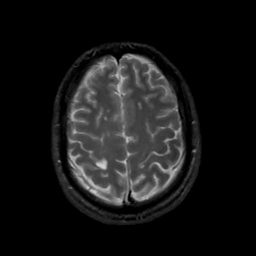

MR Study #15, June 9, 1991 -- Slice #39

[Home][Help][Clinical][Tour 1][Tour 2] Slice 39